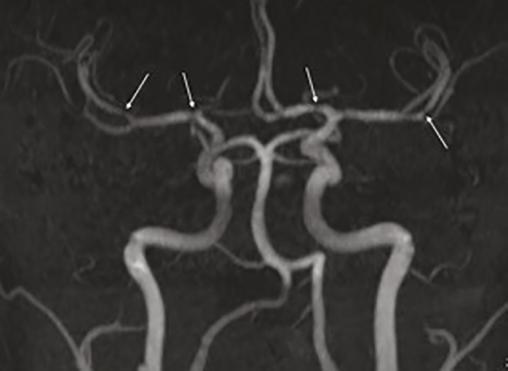

L’imagerie par résonance magnétique cérébrale réalisée retrouve un aspect évocateur de syndrome de vasoconstriction cérébrale réversible avec des sténoses multifocales, segmentaires, alternant avec des segments dilatés touchant les artères de moyen calibre (fig. 1). Il n’existe pas de lésion ischémique ou hémorragique.

Dans le SVCR, l’imagerie cérébrale avec acquisition angiographique initiale peut être normale et doit donc être répétée. L’aspect radiologique typique est une alternance de vasoconstrictions et de dilatations artérielles segmentaires et diffuses en « collier de perles ».